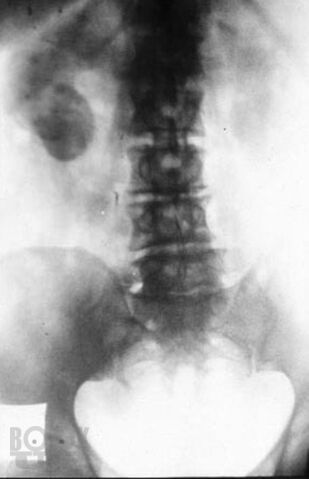

Туберкулез мочеполовой системы

Кратко изложены вопросы этиологии, патогенеза, классификации, диагностики илечения туберкулеза мочеполовой системы. Пособие подготовлено с учетом требований ФГОС ВПО (приказ Минобрнауки РФ от 31.05.2011 г. № 1975), соответствует типовой образовательной программе по специальности 060101 «Лечебное дело», предназначено для студентов 4–5 курсов лечебного факультета и направлено на формирование профессиональных компетенций вих будущей лечебно-диагностической, реабилитационной и профилактической деятельности (ПК 10, 14, 20, 26, 35).